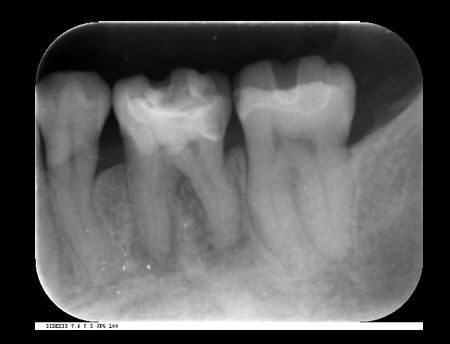

歯の根の治療(神経の治療)